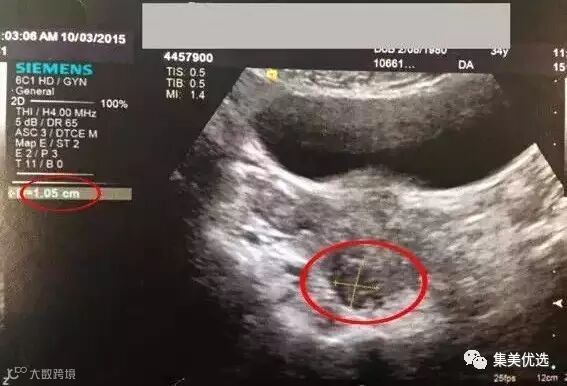

(上图为网友提供的医生B超诊断书)

(上图为网友提供的B超图)

三个月之后,我去医院做B超复查,结果太让我惊喜了!医生告诉我,4厘米的子宫肌瘤,已经缩小到1厘米左右!缩小了近四分之三!医生说,这样大小的子宫肌瘤,完全不会对身体有什么不良影响!医生建议我停用圣洁莓,并且继续坚持锻炼和注意饮食的均衡!